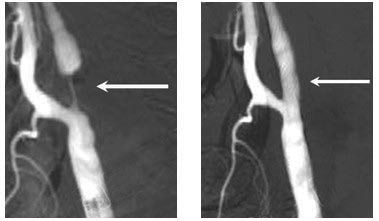

典型病例一:

患者,男,74岁,因“头晕,记忆力下降1年”入院。DSA提示左侧颈内动脉重度狭窄,予以支架置入治疗,支架置入后上述症状明显缓解。

治疗前 治疗后